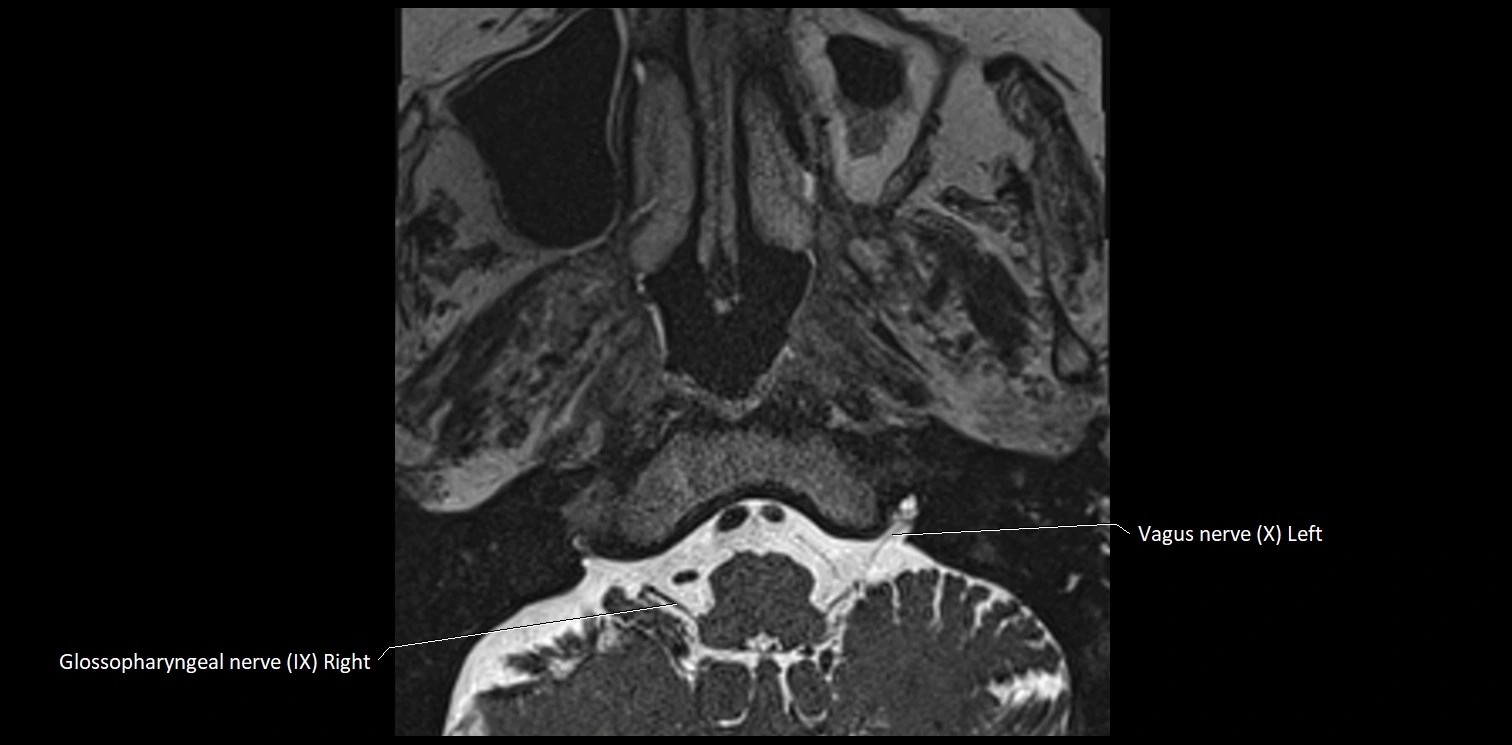

MRI Appearance

• The abducens nerve is a small, thin, linear structure

• Best visualized on high-resolution T2-weighted 3D MRI sequences (e.g., FIESTA or CISS)

• Seen as a hypointense (dark) line running from the brainstem at the pontomedullary junction, traversing the prepontine cistern, and entering Dorello’s canal under the petrosphenoidal ligament, then into the cavernous sinus, and finally the orbit

• May be challenging to visualize in standard MRI due to its small size

• Pathology may be inferred by absence, displacement, or enhancement of the nerve